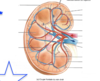

Quelles sont les deux faces du reins?

- convexe, externe

- concave, interne fait face à la colonne vertébrale (fente verticale ou hile au niveau duquel: uretère, nerfs issus du SNS*, artère et veine rénales, ainsi que vaisseaux lymphatiques)

Quelles sont les 3 zones du rein?

- externe (cortex rénal)

- intermédiaire (médullaire rénal ou médulla)

- interne (bassinet)